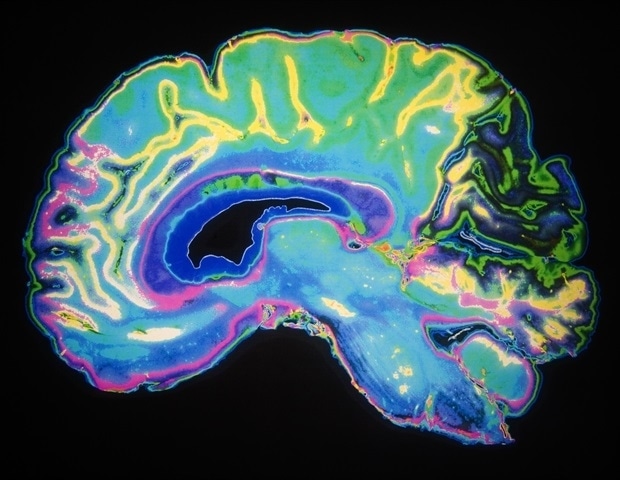

Ερευνητές από το VIB και το Πανεπιστήμιο Γάνδης έχουν ανακαλύψει και χαρακτηρίσει μια προηγουμένως άγνωστη κυτταρική ασπίδα στον εγκέφαλο, η οποία ρίχνει νέο φως στο πώς προστατεύεται ο εγκέφαλος από τον υπόλοιπο οργανισμό. Σε μια μελέτη που δημοσιεύθηκε στο Nature Neuroscience, οι επιστήμονες αποκαλύπτουν επίσης μια νέα διαδρομή μέσω της οποίας το ανοσοποιητικό σύστημα μπορεί να επηρεάσει τον εγκέφαλο.

Η πιο γνωστή από αυτές τις ασπίδες είναι η αιματοεγκεφαλική φράγμα, αλλά μια άλλη κρίσιμη διάταξη είναι ο χοριοειδής πλέγμα, μια μικρή δομή που βρίσκεται μέσα στους υγρούς χώρους του εγκεφάλου και παράγει το εγκεφαλονωτιαίο υγρό. Παρά τη σημασία της, οι επιστήμονες γνωρίζουν ελάχιστα για τη λεπτομερή κυτταρική δομή του χοριοειδούς πλέγματος και πώς προστατεύει τον εγκέφαλο.

Η ερευνητική ομάδα από το εργαστήριο της Βαντενμπρόκε επιχείρησε να ξετυλίξει αυτό το μυστήριο. Χρησιμοποιώντας προηγμένες τεχνικές αλληλουχίας γονιδίων και μικροσκοπία υψηλής ανάλυσης, εντόπισαν έναν μοναδικό πληθυσμό κυττάρων που βρίσκονται στη βάση του χοριοειδούς πλέγματος, τα οποία ονόμασαν βασικά κυτταρικά φράγματα. Αυτά τα κύτταρα συνδέονται μεταξύ τους μέσω σφιχτών συνδέσεων, οι οποίες αποτελούν ουσιαστικά μια ασπίδα. Αυτή η φράγμα παρέχει λειτουργική διαχωριστικότητα μεταξύ του χοριοειδούς πλέγματος, του εγκεφάλου και του εγκεφαλονωτιαίου υγρού.